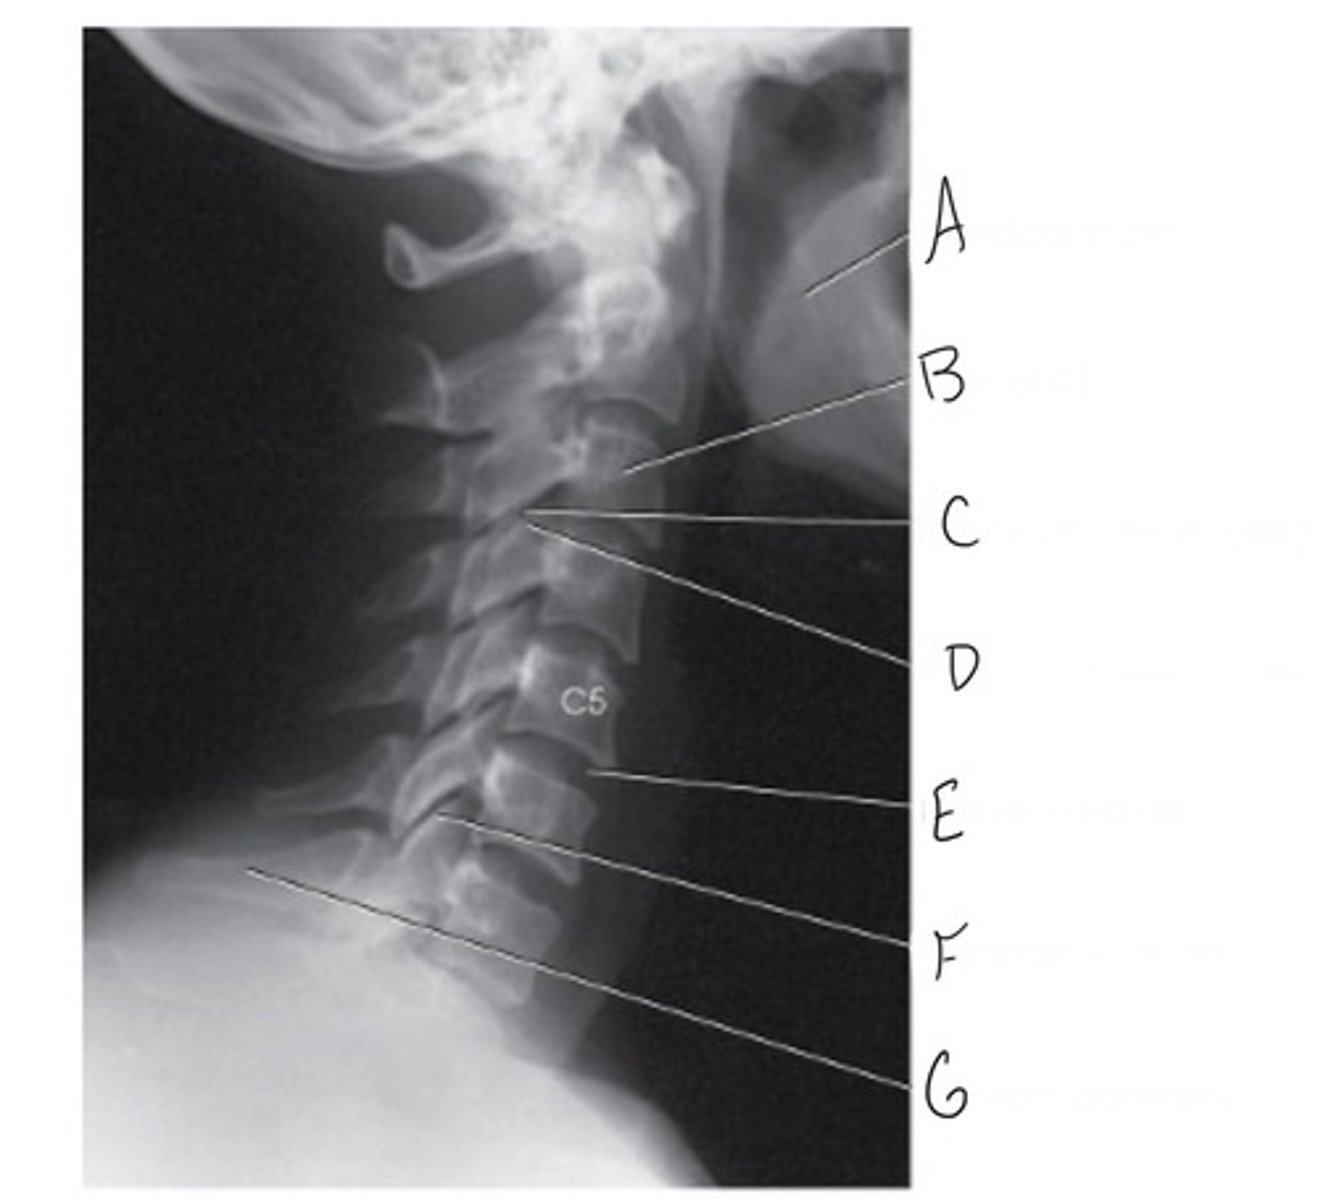

Mandibular rami

What is A?

Body of C3

What is B?

Inferior articular process

What is C?

Superior articular process

What is D?

Intervertebral disk

What is E?

Zygapophyseal joint

What is F?

Vertebra prominens (C7)

Why is G?